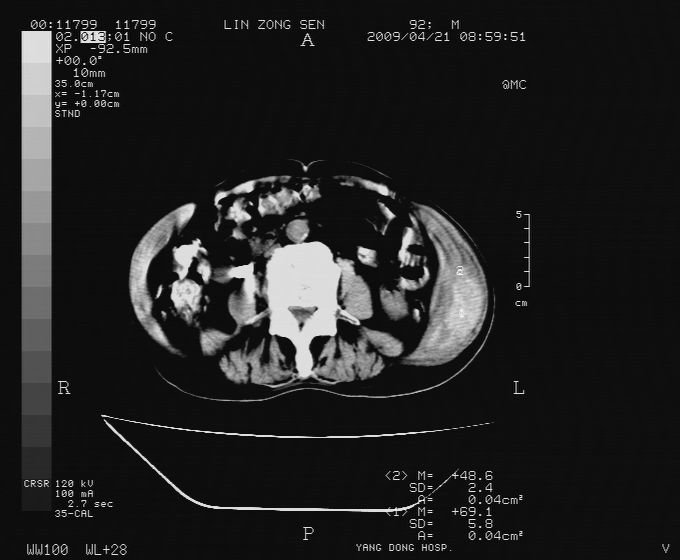

以下是引用卜一在2009-4-22 4:08:00的发言:[br]右肾积水伴输尿管上段积水!左侧肾多发囊肿!左侧腹壁软组织增厚,层次模糊,内密度较高—不排除血管瘤伴出血!